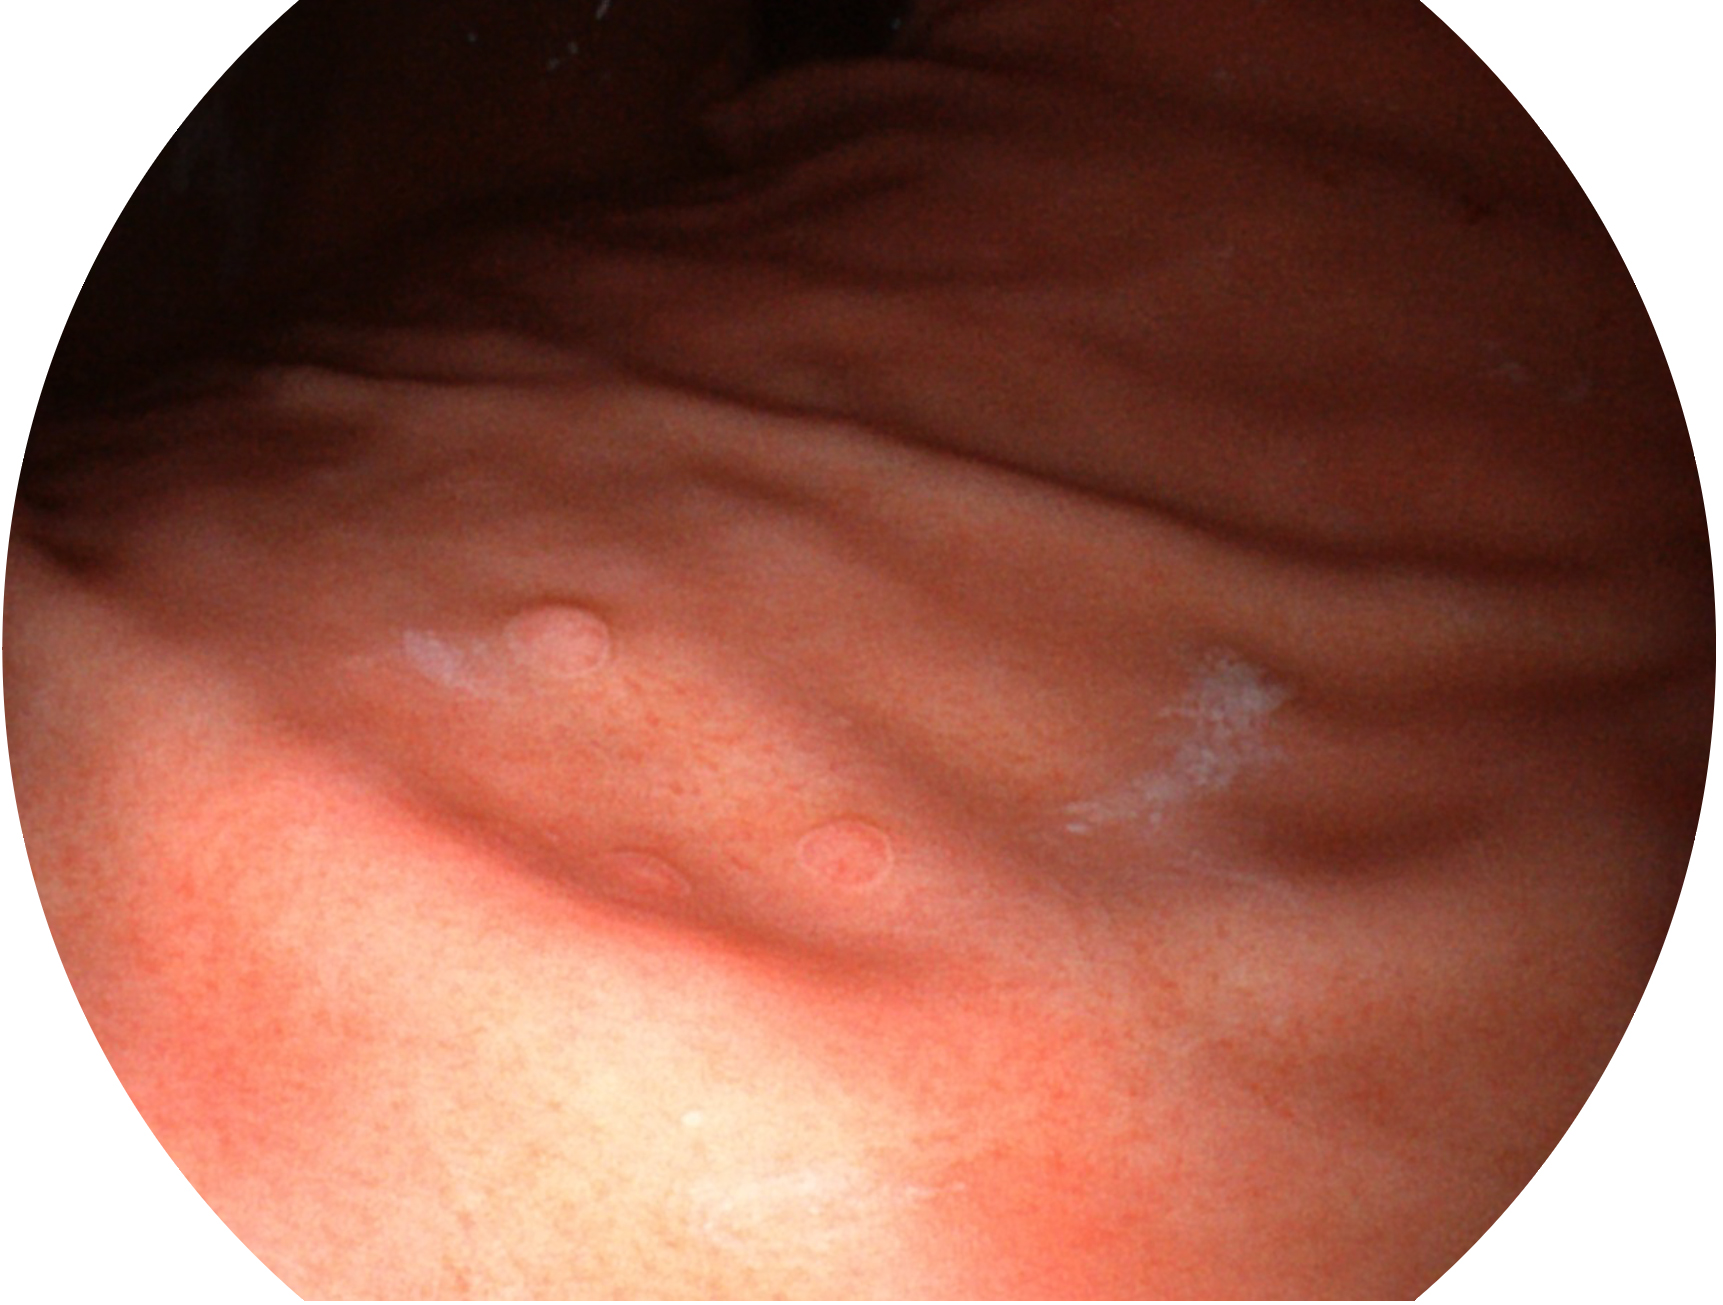

開立新開發(fā)的內(nèi)鏡染色技術(shù),主要是基于多波長LED 光源的開發(fā),VLS-55Q 四波長LED 光源是由四個(gè)不同顏色的LED光按照相應(yīng)照明模式所規(guī)定的特定發(fā)光比例進(jìn)行合束后形成,合束后形成的照明光的光譜由紅光、綠光、藍(lán)光及藍(lán)紫光這四個(gè)不同的波段范圍構(gòu)成。具有更高光譜自由度,通過光譜比例的控制,實(shí)現(xiàn)了聚譜成像技術(shù),英文全稱為“Spectral Focused Imaging, SFI”,縮寫為“SFI”和光電復(fù)合染色成像技術(shù),英文全稱為“Versatile Intelligent Staining Technology, VIST”,縮寫為“VIST”。